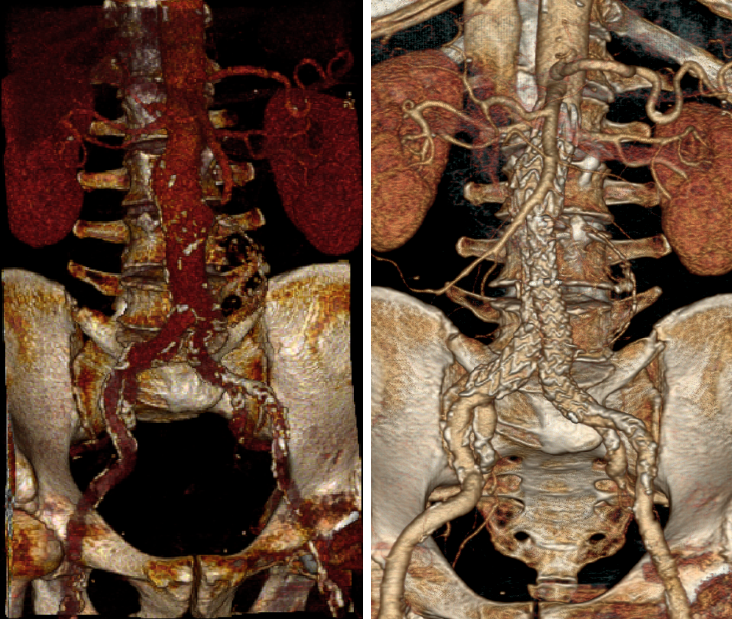

患者男性,73岁,腹主动脉瘤,高血压、血脂异常、慢性肾病。右侧股动脉中度钙化,直径5.4mm,入路面临挑战。选用Minos覆膜支架进行治疗,手术过程顺利,术后1个月的CT扫描显示无内漏且肢体通畅。该案例体现了Minos覆膜支架的Low Profile的低外径输送系统能够在狭窄和迂曲的动脉中顺利操作,为因血管条件不佳而不适合传统EVAR的患者提供了新的治疗选择。